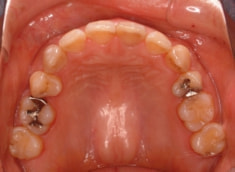

治療前